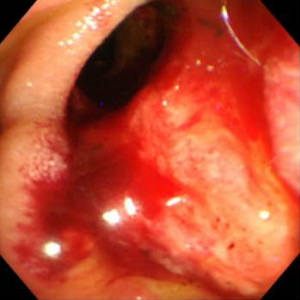

胆管癌

検診などで、採血異常から指摘されたり、黄疸で発見されたりする疾患です。正確に診断をつけるため、胆道造影を行い、病変から直接細胞や組織をとり治療方針を決定していきます。胆管ファイバーやIDUSなども必要に応じ施行しております。閉塞性黄疸をきたしている場合は胆管ドレナージを行います。